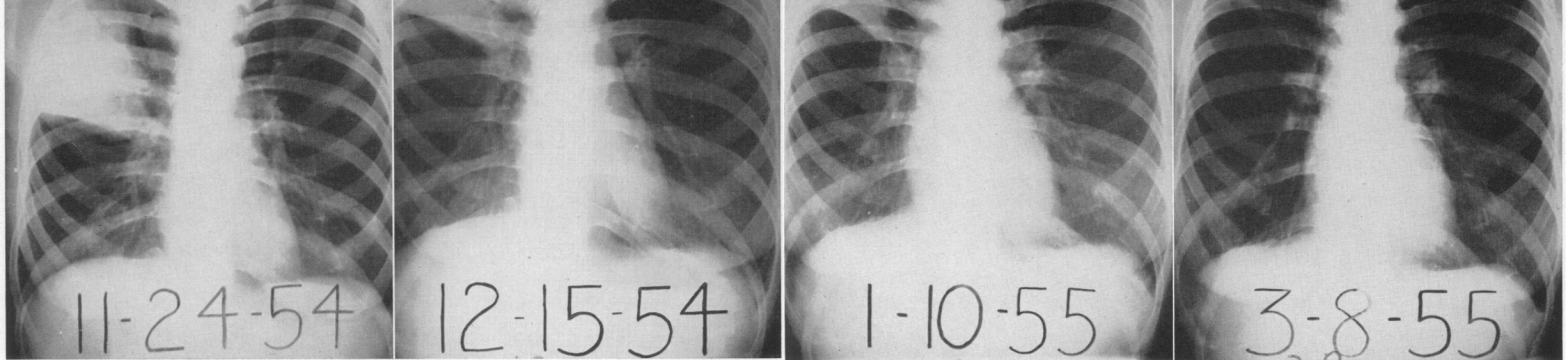

Around day 5, bacteria have been removed, and neutrophils are no longer the main immune cell. And yet we still see an infiltrate on CXR. In fact, early studies suggest that consolidations remain for up to 6-8 weeks.

Image credit: Kirby, W. M., Waddington, W. S., & Francis, B. F. (1957). Differentiation of right-upper-lobe pneumonia from bronchogenic carcinoma. New England Journal of Medicine, 256(18), 828-833.